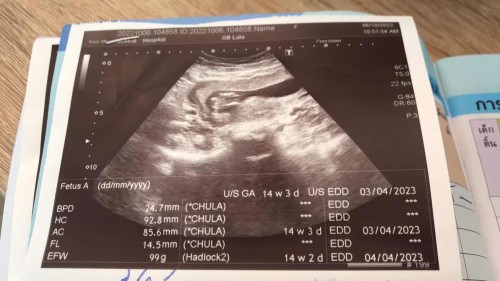

ตอนนี้ท้องได้13สัปดาห์กว่าแล้วค่ะ เมื่อวาลคุณหมอนัดไปซาว ฝากที่ รพ ประจำ อำเภอ คะ คุณหมอแจ้งแม่ว่าน้องตัวเล็ก น้ำหนักก็น้อย น้ำหนักน้อง 99g ตามที่คุณหมอแจ้ง ตอนนี้แม่กังวลมาก กลัวลูกจะเป็นอะไร แม่ๆท่านไหนรู้หรือให้คำปรึกษาได้ ได้นะคะ ตอนนี้แม่กลัวไปหมด จากคำพูดของคุณหมอ หมอนัดเจาะเลือดตรวจดาว วันที่20ตุลานี้ค่ะ #ขอคำแนะนำหน่อยค่ะ #คุณแม่ๆช่วยแนะนำหน่อยค่ะ